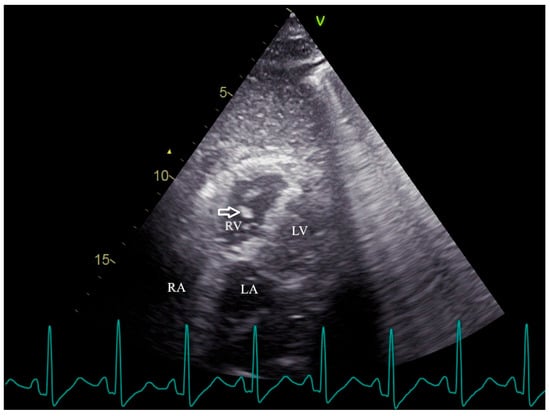

| LA | Left atrium |

| LV | Left ventricle |

| RV | Right ventricle |

| RVFAC | Right ventricular fractional area change |

| TTE | Transthoracic echocardiography |